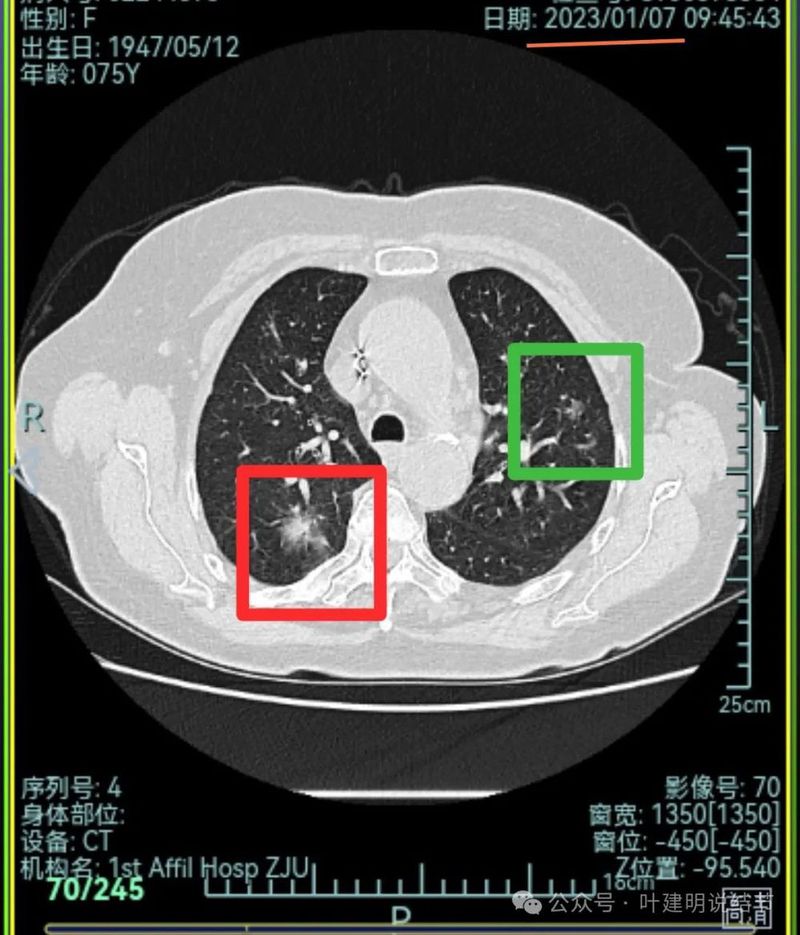

先来看2023年1月时的影像:

右上叶混合密度病灶,有毛刺征,轮廓较清,单次单处看是要考虑恶性的;左上叶磨玻璃结节,轮廓较清,密度较淡,瘤肺边界部分边缘稍不清。

右上叶混合密度结节了,瘤肺边界欠清,周围有晕;左上叶磨玻璃结节,有毛刺征,整体轮廓较清,瘤肺边界略显糊。